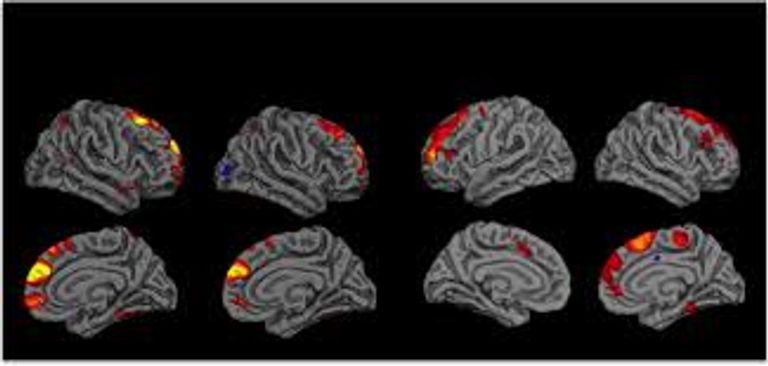

ووفقا للباحثين، فإن هذا المثبط يعمل كـ"فلتر" يمنع القدرات النفسية والتخاطرية، مثل الاتصال الذهني (التخاطر)، والتنبؤ بالمستقبل (التبصر)، وتحريك الأشياء باستخدام العقل (التحريك الذهني، لكن عند تعطيل هذا الفلتر باستخدام تقنيات حديثة، مثل التحفيز المغناطيسي عبر الجمجمة، تزداد هذه القدرات بشكل ملحوظ.

وقد شملت الدراسة، التي نشرت في مجلة "كورتكس" في عام 2024، تجارب على 108 متطوعين تم تقسيمهم إلى مجموعات تلقت تحفيزا مغناطيسيا مختلفا لأجزاء من الدماغ، وكانت المجموعة التي تلقت التحفيز على الجزء الأيسر من الفص الجبهي الأوسط هي الوحيدة التي أظهرت زيادة ملحوظة في قدراتها التخاطرية.